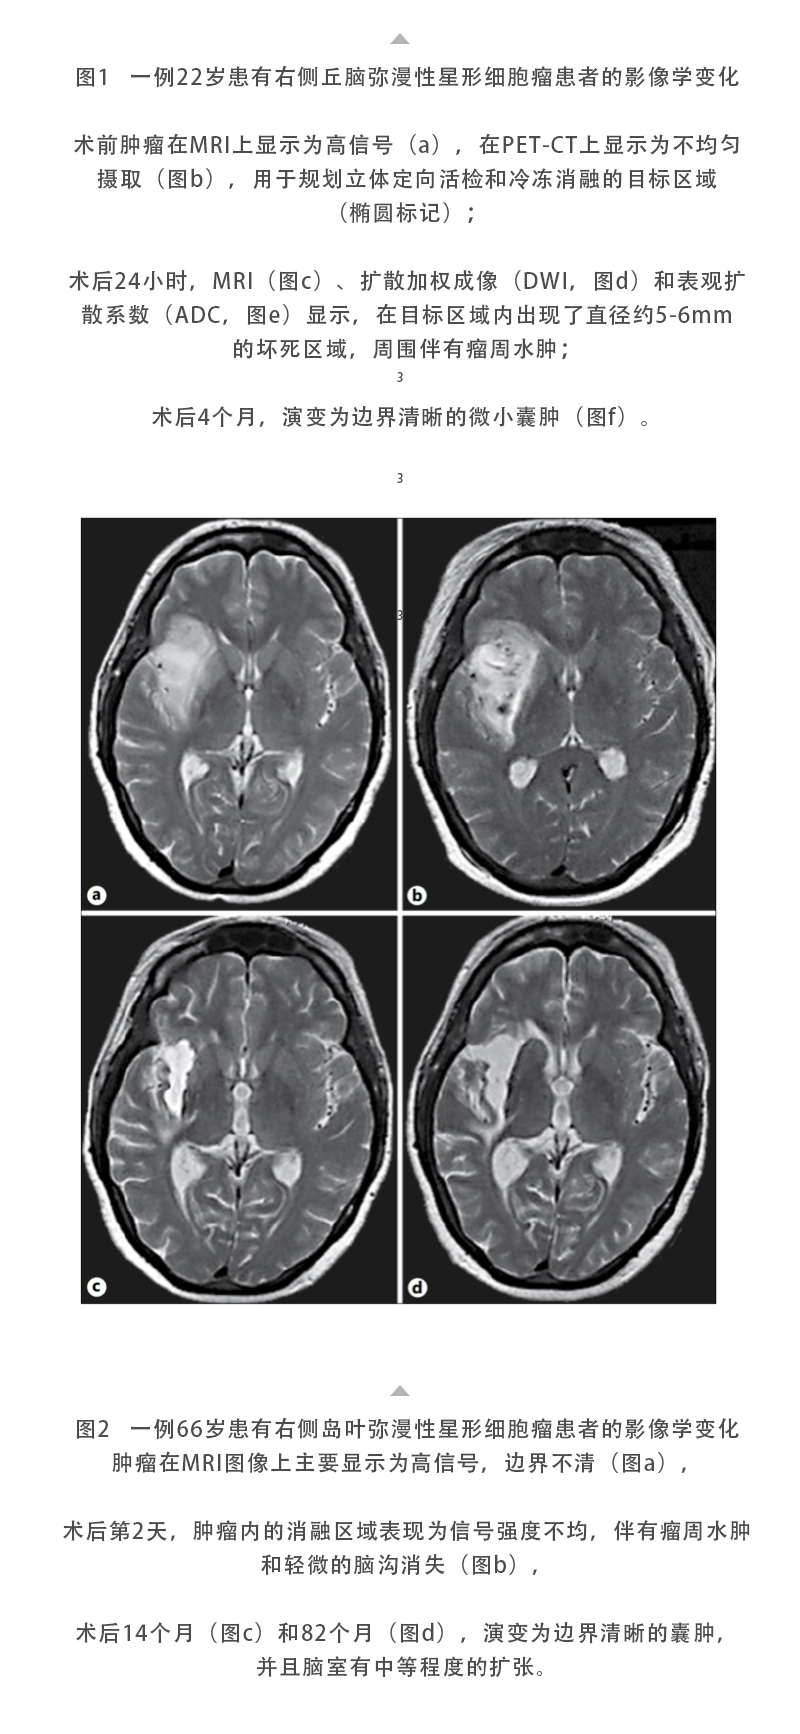

冷凍消融腦膠質(zhì)瘤——【海杰亞科研資訊】第283期